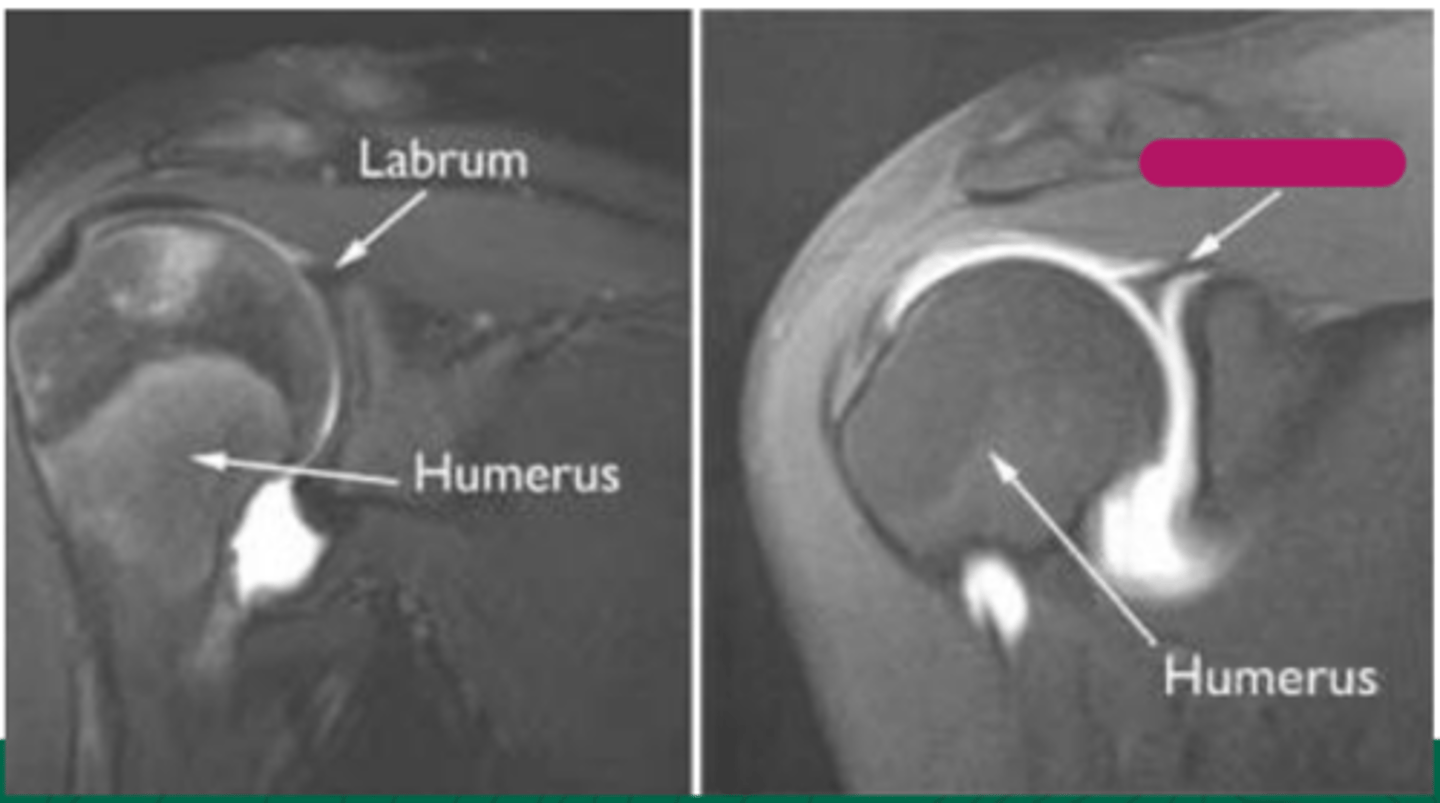

SLAP tear

What does the image show?